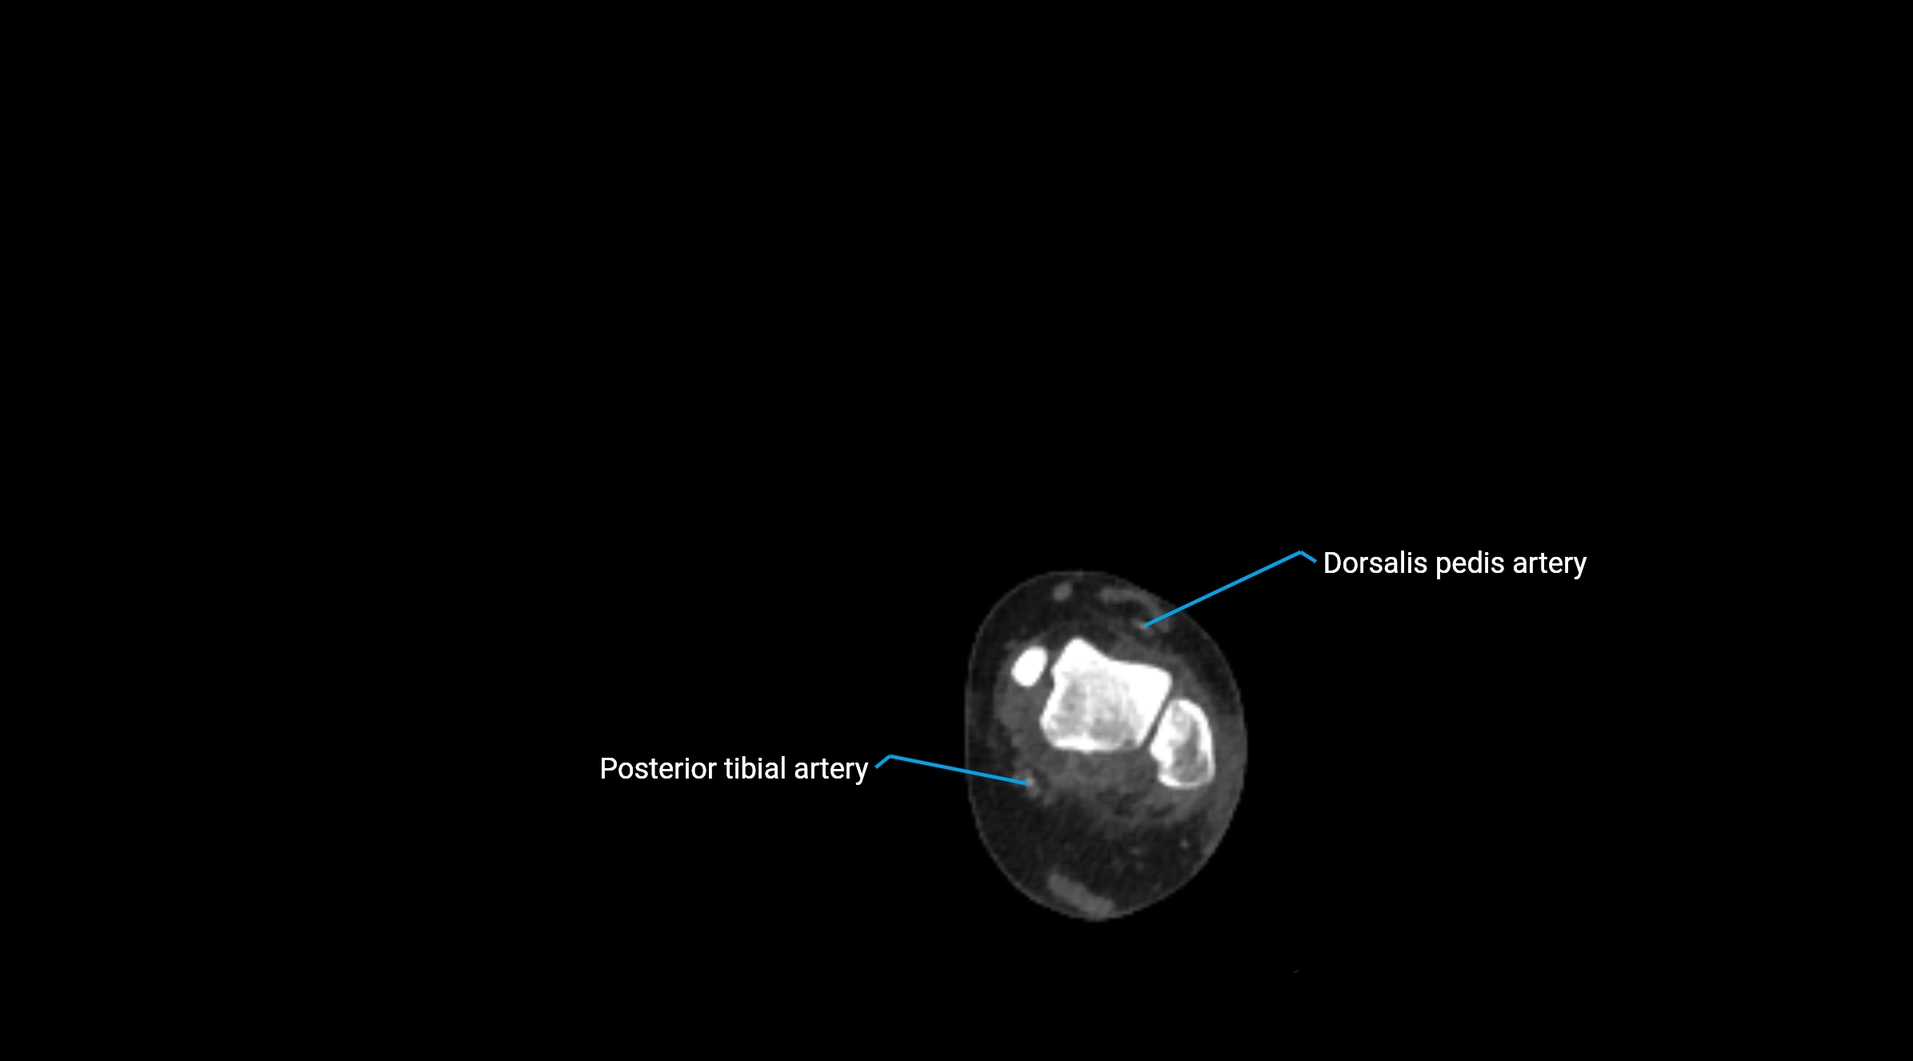

CT Appearance

Non-contrast CT:

• Appears as a tubular soft tissue structure anterior to vertebral bodies

• Calcified atherosclerotic plaques appear as hyperdense foci along the wall

• Useful for screening abdominal aortic aneurysm (AAA) size and mural calcification

Contrast-enhanced CT (CTA):

• Gold standard for abdominal aortic imaging

• Provides excellent detail of lumen, wall, aneurysm, thrombus, and branch vessels

• Multiplanar and 3D reconstructions help in aneurysm measurement, stent graft planning, and dissection evaluation

• Detects acute rupture, traumatic injury, or occlusion with high sensitivity